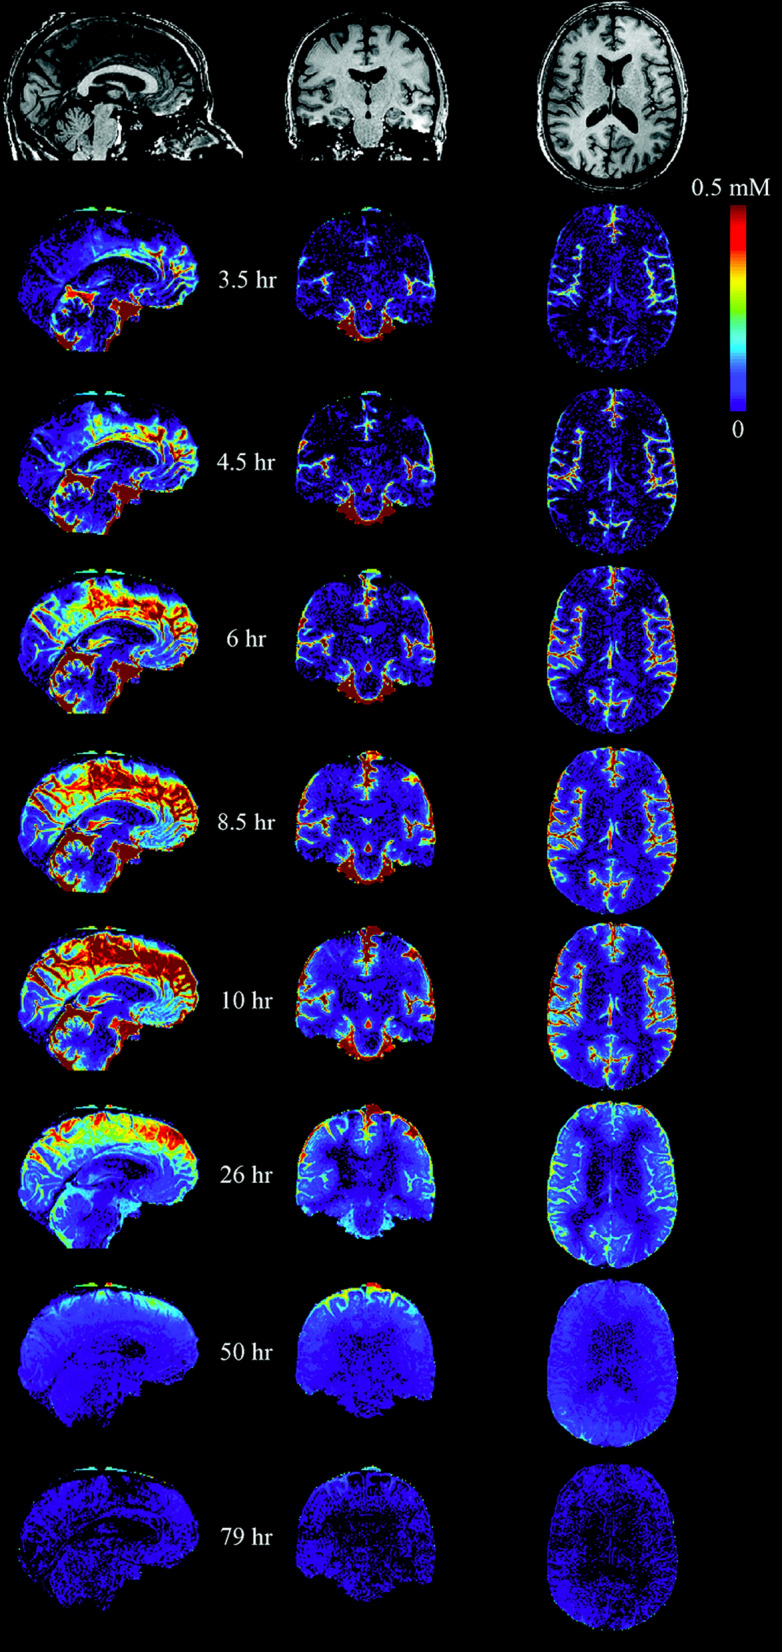

Watts et al. [117] obtained data from a human using an MRI extracellular fluid marker, the contrast agent gadobutrol, but as of the time of this review a kinetic analysis of these data has not been published. Bearing in mind the previous results with rodents, the most remarkable feature of the results for the single human subject in Fig. 6 is the long time scale, which echoes an earlier result of Eide et al. [166]. However, without detailed analysis it is difficult to establish with any confidence whether the slow steps represent the distribution and outflow of CSF or the entry into and exit from the parenchyma of the contrast agent. The persistence of the agent in the parenchyma whilst that in the CSF had been reduced suggests that efflux from the parenchyma and hence also influx were slow. This argues that the proportion of gadobutrol crossing into the parenchyma was low.15 A full study with analysis of data from more than one experimental subject would be very informative.

Fig. 6.

Human MRI images showing changes in gadobutrol concentration following an intrathecal injection. At t = 0, 1 µmol of gadobutrol was injected into the subarachnoid space of the spinal cord. It reached the cisterna magna in about 3 h and spread over the surface of the brain in the next 7-8 h. Note that the gadobutrol concentrations on the dorsal surface of the brain persist for longer than in the basal cisterns as expected if elimination of gadobutrol occurs primarily from the cisterns, e.g. across the cribriform plate, but not from the dorsal subarachnoid spaces. The partial analysis of these data in [117] shows that in various regions of the brain the concentrations in grey matter are still increasing up to 12 h and subsequently decrease over days in parallel with that in CSF adjacent to the region. However, even at their maximum they are less (2 to 5 fold depending on region) than the concentrations that were achieved in the adjacent subarachnoid spaces. At the very latest times, the concentrations in parenchyma appear to exceed the then current concentrations in adjacent subarachnoid spaces. The subject was awake from the time of administration until after the scan at 10 h and had a normal nights sleep before each of the last three scans. Figure taken with permission from Watts et al., Am. J. Neuroradiol., 2019 [117]